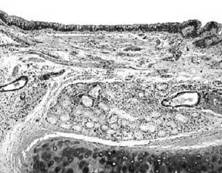

非特異性慢性炎,病變主要表現為纖維母細胞、血管內皮細胞和組織細胞增生,伴有淋巴細胞、漿細胞和巨噬細胞等慢性炎細胞浸潤,同時局部的被覆上皮、腺上皮和實質細胞也可增生。慢性炎症還可伴有肉芽組織的形成,這類炎症常見於有較大的組織缺損,此時肉芽組織在慢性膿腫、瘺管和慢性黏膜潰瘍的吸收和分解上起著重要作用。

慢性炎症(1)乾酪樣壞死:典型結核結節的中央為乾酪樣壞死,內含壞死的組織細胞和白細胞,還有結核桿菌。結核結節中心的壞死可能是細胞介導免疫反應的結果。

(2)類上皮細胞(epithelioidcell):乾酪樣壞死灶周圍可見大量胞體較大、境界不清的細胞。這些細胞的胞核呈圓形或卵圓形,染色質少,甚至可呈空泡狀,核內可有1~2個核仁,胞漿豐富,染成淺紅色。根據其形態與上皮細胞相似,故稱類上皮細胞。

(3)多核巨細胞(multinucleatedgiantcell);在類上皮細胞之間散在多核巨細胞,結核結節之多核巨細胞又稱為Langhans巨細胞。這種巨細胞體積很大,直徑達40~50μm。胞核形態與類上皮細胞相似,數目可達幾十個,甚至百餘個,排列在細胞周邊部呈馬蹄形或環形,胞漿豐富。Langhans巨細胞系由類上皮細胞融合而成;類上皮細胞首先伸出胞漿突起,然後胞體相互靠近,最後經胞漿突起的融合使類上皮細胞融合在一起形成多核巨細胞。但融合的機制尚有待闌明。